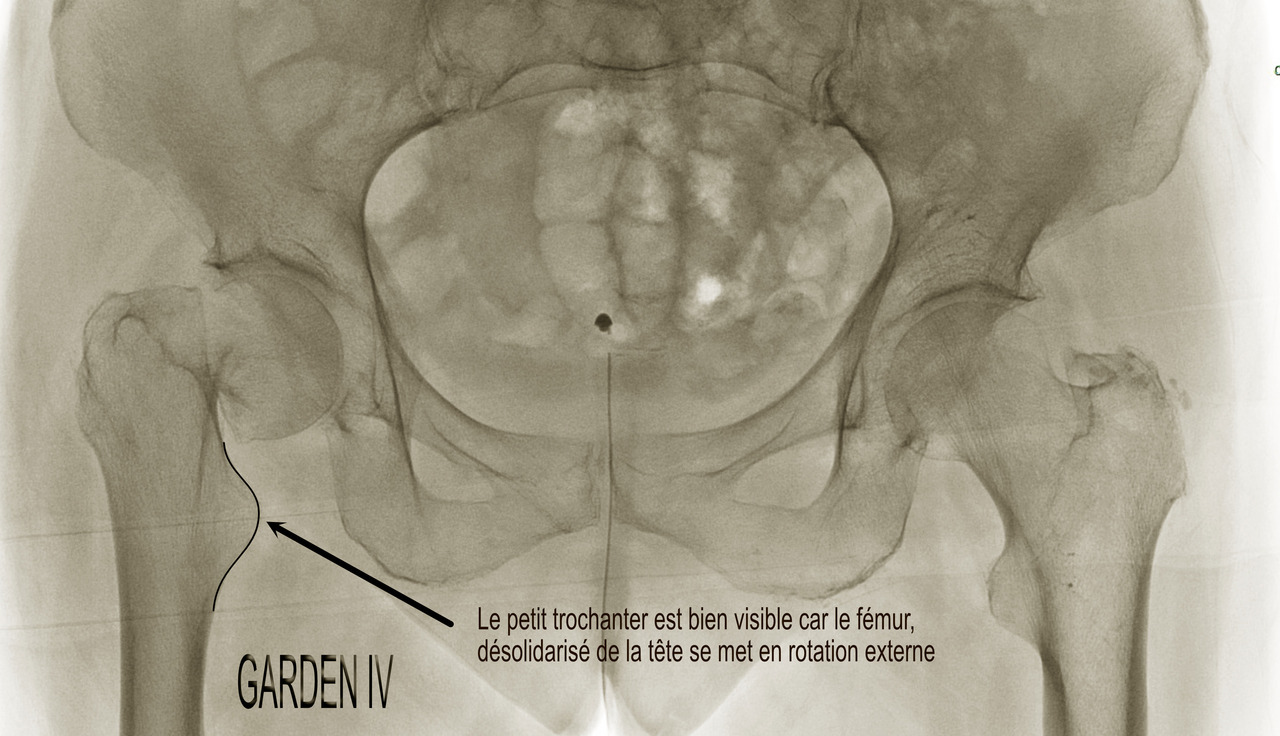

• le type IV est une fracture déplacée avec perte de contact des fragments, notamment au niveau de la charnière, augmentant encore le risque de nécrose au-delà de 50 %. Son aspect radiographique est souvent éloigné des schémas car, du fait de la désolidarisation complète entre le fémur et la partie proximale de la tête et du col, il se produit une rotation externe complète du fragment distal (fig. 9), comme en témoigne le déroulement du petit trochanter particulièrement visible dans ce cas-là.